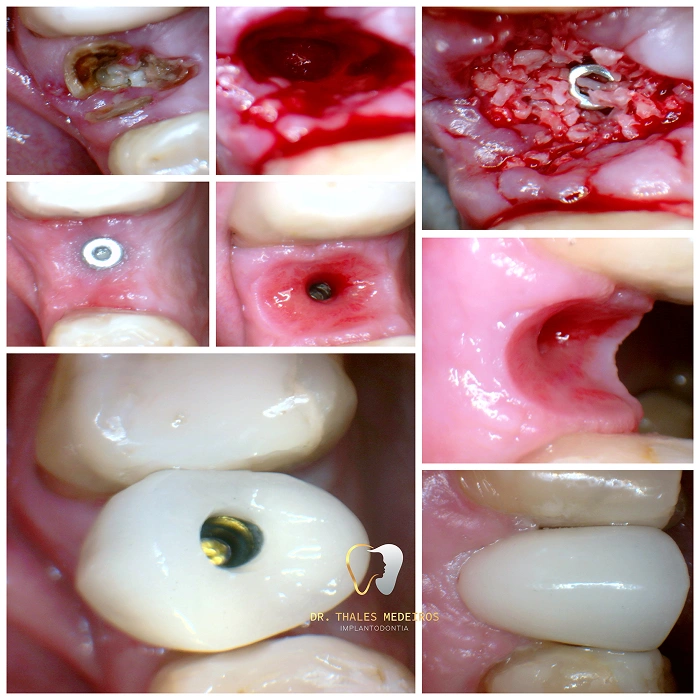

Implantes Dentários: Sorrisos restaurados com segurança e precisão

Recupere seu sorriso e sua qualidade de vida com os implantes dentários do Dr. Thales Medeiros. Com 9 anos de experiência e quase 2.000 implantes realizados, ele é referência na Paraíba em reabilitação oral. Os implantes proporcionam benefícios como restauração da mastigação, preservação da estrutura óssea, estabilidade dentária duradoura, melhora da estética do sorriso e aumento da autoestima.

Cada procedimento é planejado de forma personalizada, unindo tecnologia de ponta e cuidado humanizado para oferecer resultados seguros e naturais.

Cirurgia Plástica Periodontal e Periimplantar

Recupere a estética e a saúde do seu sorriso com a cirurgia plástica periodontal e periimplantar. O procedimento corrige retrações gengivais, remodela os contornos e prepara o sorriso para implantes e facetas. Entre os principais benefícios estão gengivas mais saudáveis, sorriso simétrico, harmonia estética e aumento da autoestima, garantindo resultados naturais.